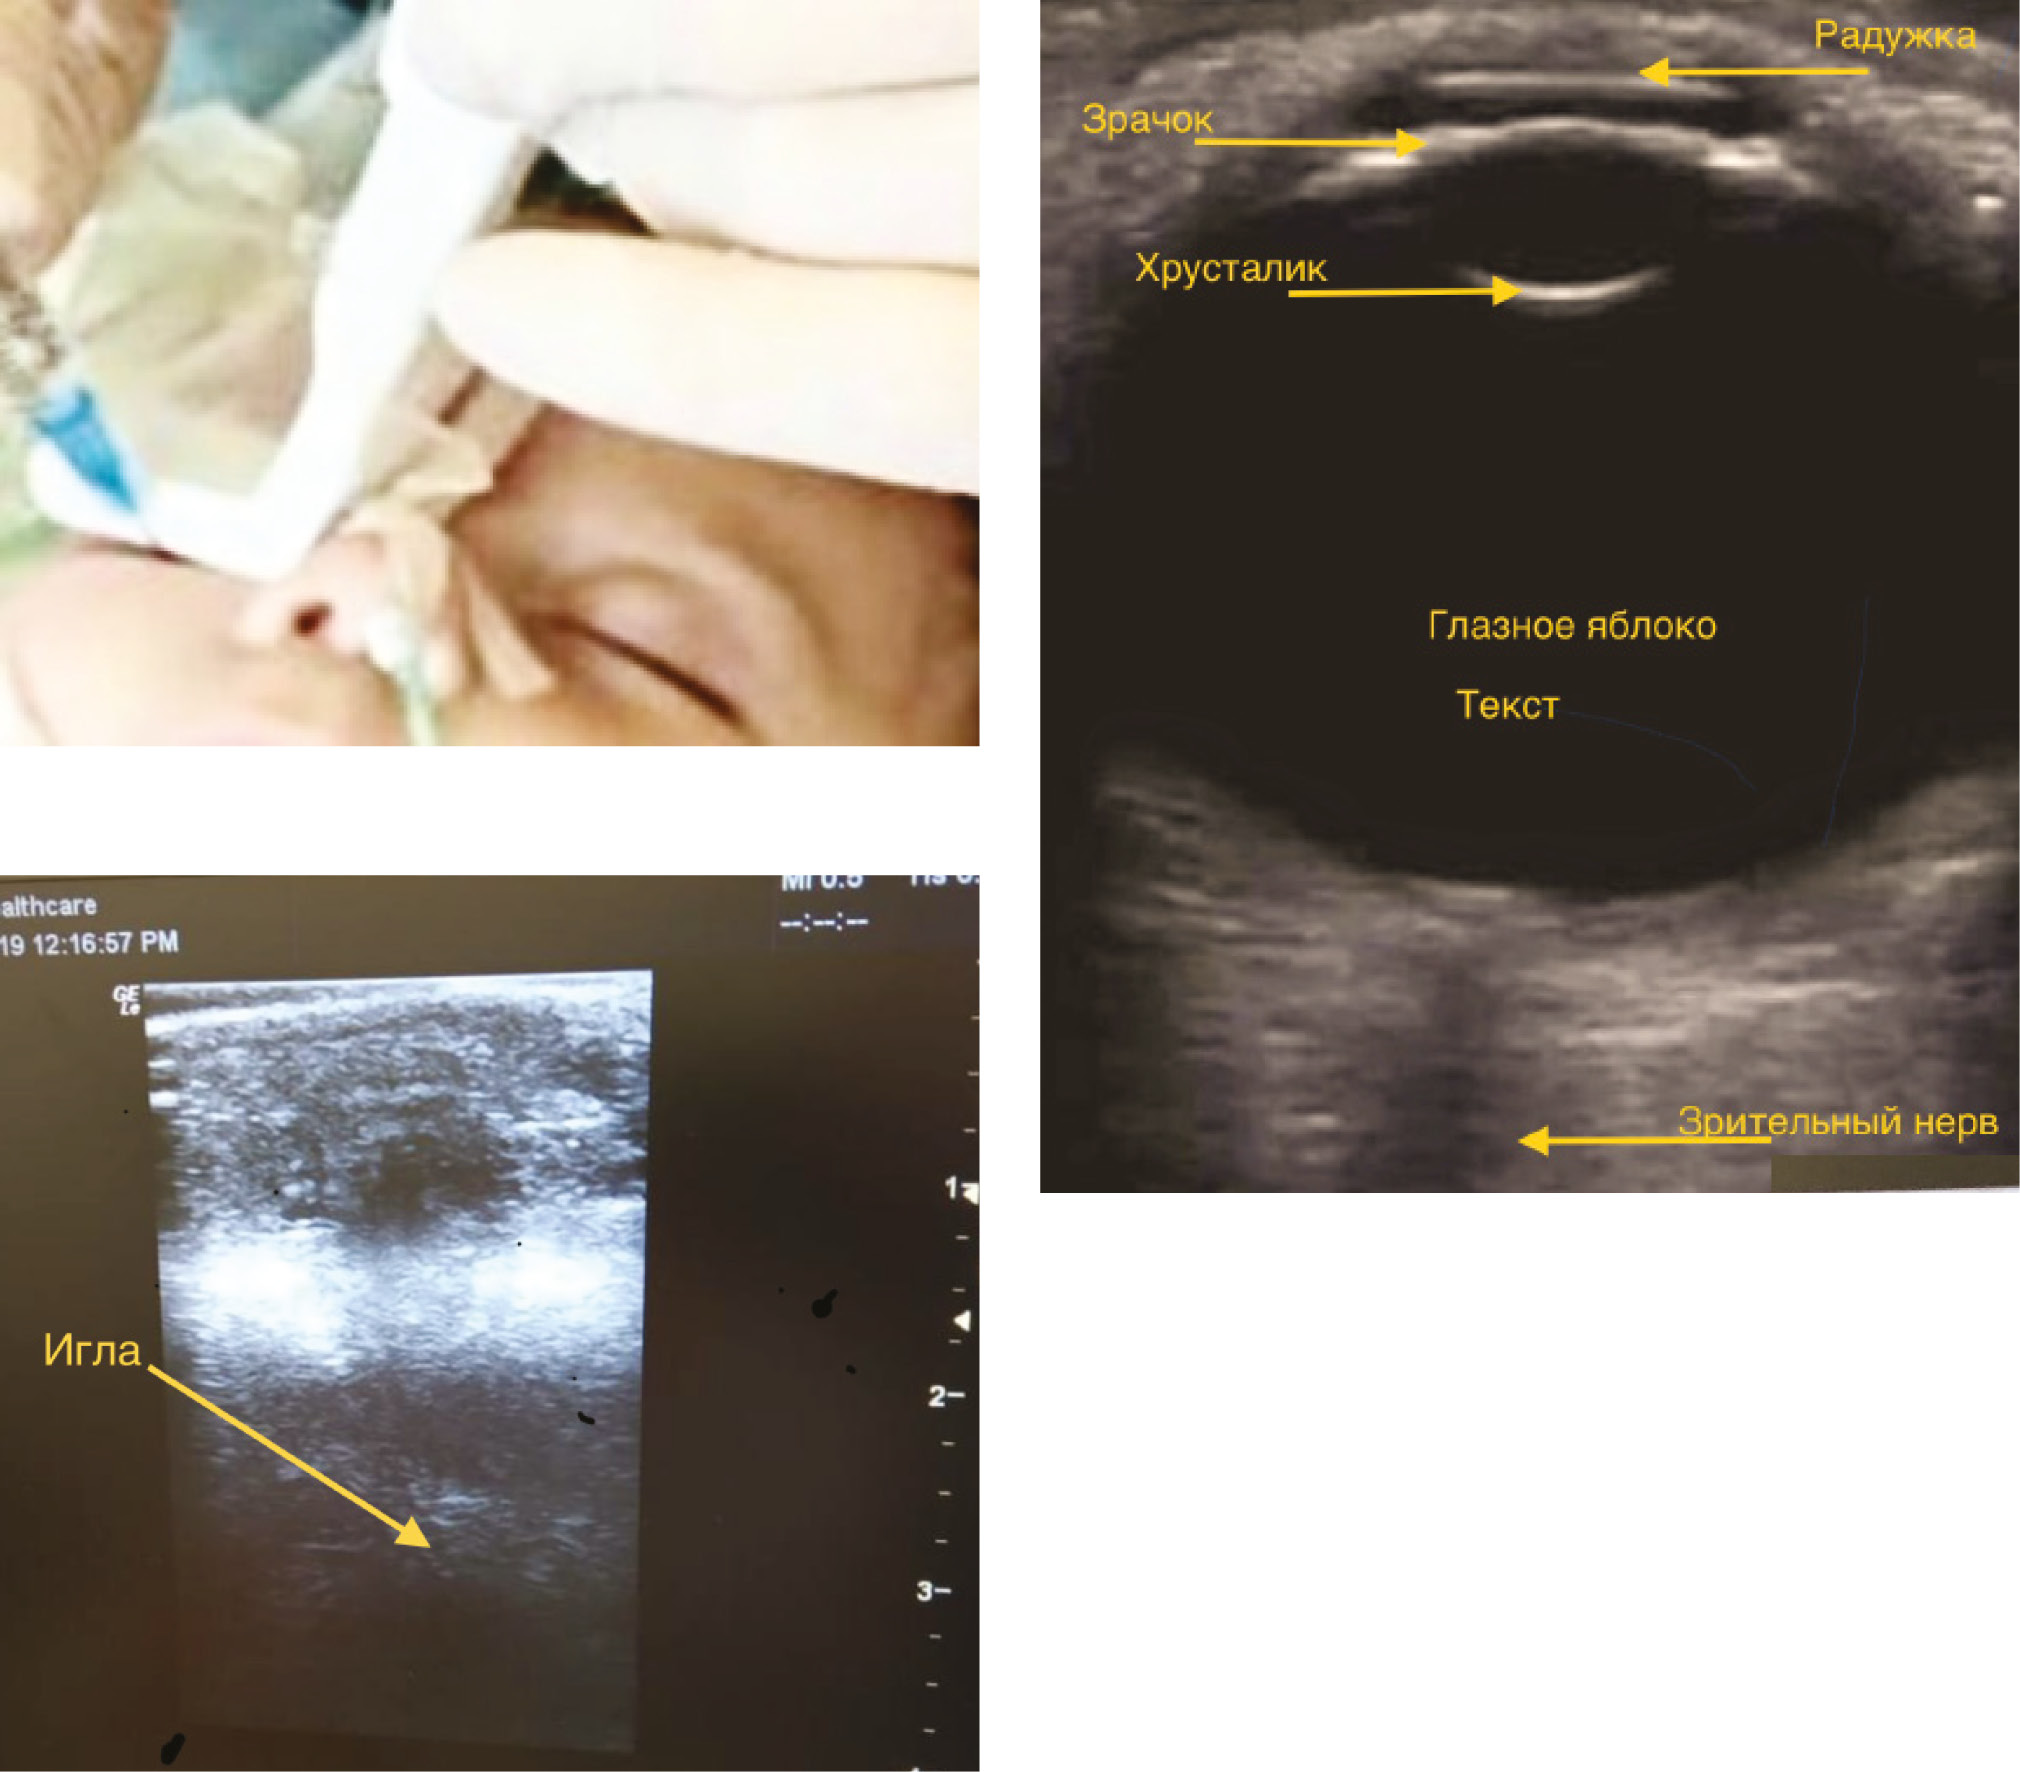

В группе РББ+УЗИ – в условиях ОА и ИВЛ после обработки кожи местным антисептиком, на закрытое нижнее веко помещался линейный интраоперационный датчик с длиной волны 4–12 МГц (ультразвуковой сканер General Electric Logiq е), изолированный стерильным материалом с предустановленной глубиной сканирования до 3,0 см. Сканирование проводилось по продольной оси, под боковым углом 10–15°, смещая глазное яблоко вверх. После визуализации интраорбитальных структур вводилась игла 23G x 25 мм в нижнем внешнем квадранте орбиты (позиция 7 ч) на одной линии с датчиком и продвигалась перпендикулярно, пока конец иглы не достигал экватора глазного яблока, затем иглу направляли к зрительному нерву (гипоэхогенная трубчатая структура в заднем отделе глазного яблока). На расстоянии 4–6 мм от него после отрицательной аспирационной пробы вводили 0,5% раствор ропивакаина 0,1 мл/кг. При правильном положении канюли пробный болюс визуализировался как смещение структур вокруг зрительного нерва за счёт гидродиссекции тканей (рис. 2).

Рис. 2. Положение датчика. Сонограмма глазного яблока и орбиты. Введение иглы в плоскости луча (in plain) справа (фотография из личного архива авторского коллектива)

Fig. 2. Sensor position. Sonogram of the eyeball and orbit. The introduction of the needle in the plane of the beam (in plain) on the right (photo from the personal archive of the group of authors)